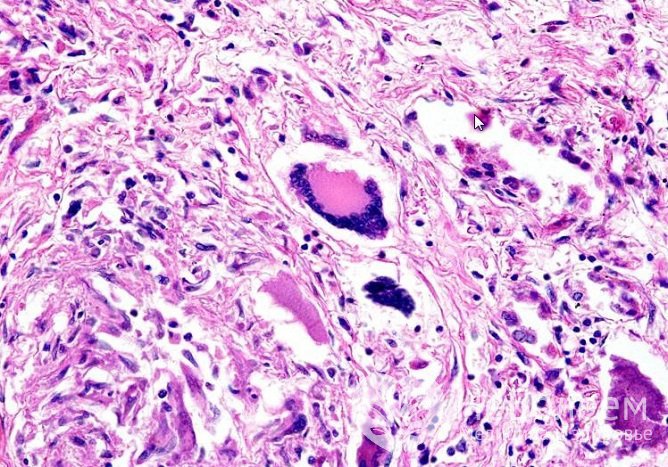

Рентгенография легких – легочные узлы при гранулематозе Вегенера

Рентгенография легких – легочные узлы при гранулематозе ВегенераПри необходимости в диагностике гранулематоза Вегенера используют и другие методы: например, компьютерную томографию или биопсию тканей верхних дыхательных путей с последующим гистологическим анализом.